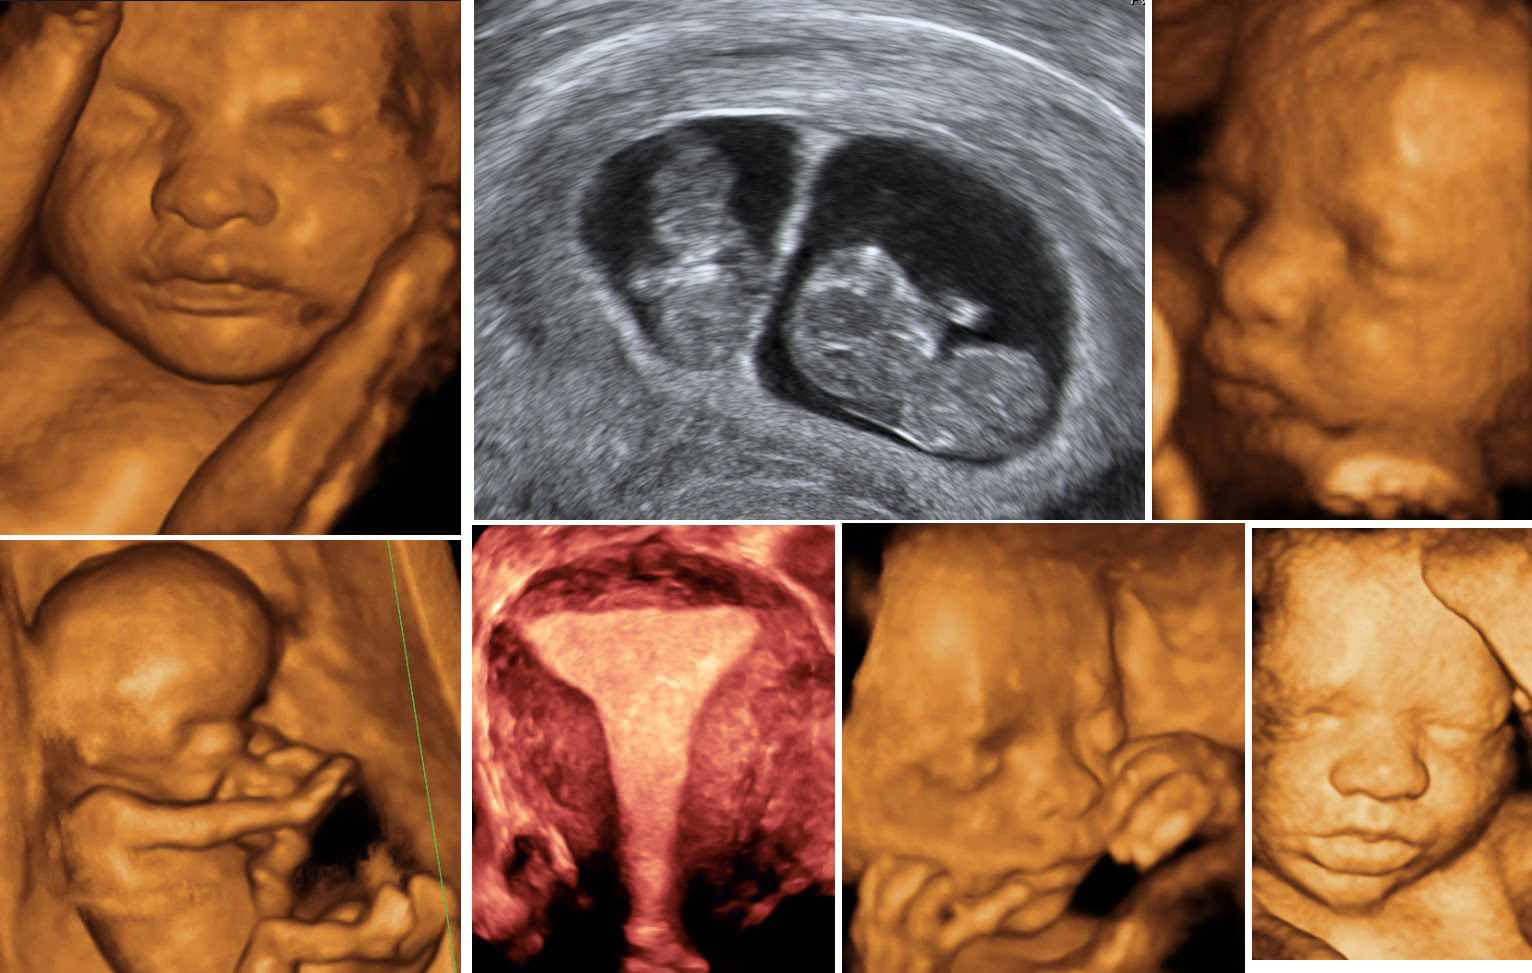

This is where the Obstetric Color Doppler comes into play, offering a solution that addresses both emotional and practical needs. The Obstetric Color Doppler is a specialized ultrasound that provides detailed images of the blood flow in the fetus, placenta, and uterus. It offers crucial insights into the baby's health and ensures timely detection of potential complications.

For Priya, scheduling an Obstetric Color Doppler examination was a pivotal step. As she lay on the examination table, the gentle hum of the machine filled the room. The doctor explained each colorful wave on the screen, depicting the flow of blood to her baby. In that moment, Priya's worries began to dissipate, replaced by a profound sense of reassurance and connection to her unborn child.

The Obstetric Color Doppler not only addressed Priya's concerns but also empowered her with knowledge about her pregnancy. It provided clarity in monitoring her baby's health, ensuring that both she and her healthcare provider could make informed decisions. This technology serves as a bridge between expectant mothers and their unborn children, fostering a deeper understanding and confidence in the pregnancy journey.

The impact of the Obstetric Color Doppler extends beyond individual experiences like Priya's. In a country like India, where access to quality prenatal care can vary significantly, this technology plays a crucial role in ensuring healthy pregnancies. It assists healthcare professionals in identifying conditions such as fetal growth restrictions, placental issues, or umbilical cord complications early on, allowing for timely interventions.

Consider another case study from Chennai, where Meena, a 32-year-old teacher, was expecting her second child. During a routine check-up, her doctor recommended an Obstetric Color Doppler due to concerns about her baby's growth rate. The detailed insights obtained from the Doppler helped detect a mild placental insufficiency. With this information, Meena's medical team implemented a tailored care plan, ensuring a smooth and healthy pregnancy outcome.